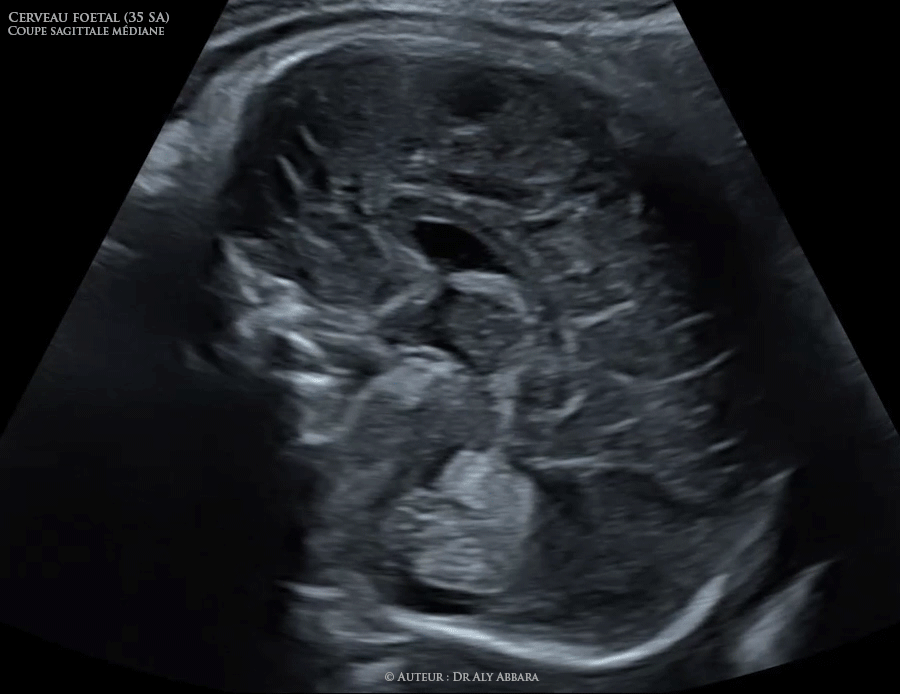

Coupe sagittale médiane du cerveau fœtal (à 35 SA) - Eléments anatomiques identifiables en échographie

Séquences vidéo et images échographiques montrant les structures anatomiques identifiables dans une coupe sagittale médiane rasant la face interne de l'un des deux hémisphères du cerveau fœtal à 35 SA du haut vers le bas :

* la face interne d'un des deux hémisphères cérébraux avec ses sillons ;

* le sillon cingulaire : le sillon le plus ancien de la face interne de l'hémisphère cérébral et le plus près du corps calleux (en étant parallèle à son corps) ;

* le corps calleux avec ses différents segments (de devant en arrière) : bec, genou, corps et splenium (ou bourrelet) ;

* le cavum septum lucidum limité en haut et de devant par le corps calleux (bec, genou et la partie antérieure de son corps), puis en bas et en arrière par le trigone (fornix) ;

* le trigone cérébral ou le fornix (formant le plancher du cavum du septum lucidum et le toit du troisième ventricule) ;

* le gyrus subcalleux (formant la paroi antérieure du troisième ventricule) ;

* le troisième ventricule avec ses trois processus (supérieur, antérieur et postérieur) ;

* la face interne du thalami (les faces internes des deux thalami "noyaux diencéphalique" forment les limites latérales de la partie postérieure du troisième ventricule) ;

* le tronc cérébral : partie supérieure = pédoncules cérébelleux ou le mésencéphale ; partie moyenne = protubérance et la partie inférieure = bulbe rachidien ;

* l'aqueduc de Sylvius est limité par le tronc cérébral (commissures des pédoncules cérébelleux = mésencéphale) en avant et le colliculi en arrière ;

* le colliculi (le toit de l'aqueduc de Sylvius) ;

* le quatrième ventricule est limité par le tronc cérébral en avant et le vermis du cervelet en arrière ;

* le vermis du cervelet.